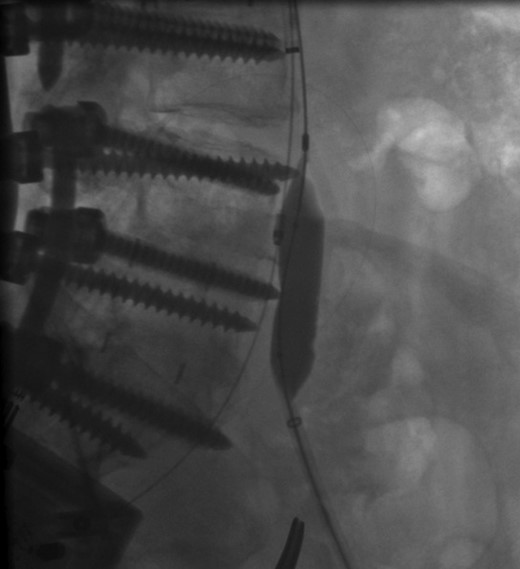

The patient was scheduled for left iliac vein stent placement. During the procedure, impingement was noted upon the posterior aspect of the vein. At this location, there was perforation of a pedicle screw through the anterior cortex of her L5 vertebral body, from prior spinal fusion. This interaction was well visualized during intraluminal inflation of a 12 mm × 40 mm high-pressure balloon (Fig. 2) and was also seen after final stent placement (Fig. 3). Because the screw tip was completely unyielding, a 14 mm × 60 mm Wallstent was used instead of the 16 mm stent we typically use, so as to avoid undue compression of her overlapping right common iliac artery. After the procedure, the patient's symptoms were greatly improved. Follow-up venography performed 4 months postoperatively showed a patent stent with slight eccentric compression at the protruding screw and no evidence of in-stent stenosis.

Intraoperative radiograph showing posterior compression of a wall stent within the left common iliac vein.